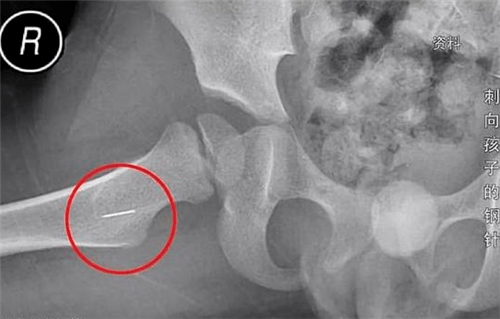

他检查发现,小晨的屁股上有个眼,一开始并没有感觉到不对劲。以为是蚊子咬的,想着涂点药就好了,可没想到第二天小晨依然不断的喊:“屁股扎!扎!”这下张先生才意识到不对劲,从头到脚又摸了一遍孩子,发现孩子屁股处竟然有一个突起。急忙带着孩子去了医院,经x光检查,医生确定的告诉他小晨左半边臀部有两个异物。

从形状上来看,像是钉子或者细针,听见这话张先生夫妇顿时红了眼睛。为取出小晨体内的针,他们辗转四家医院,长针还比较好取出。短针却已经发生位移,最后不得不接受全麻手术,伤口长达8厘米。万幸的是没有刺到要害,如果针刺到幼儿体内,可能会造成残疾。如果刺进大动脉,甚至可能造成死亡,后果难以估量。

就算是这样,这两根针的程度,也达到了轻伤二级。它们到底是怎么进入小晨体内的?查出有两根针后,基本可以确定是人为的,一根还可以说是意外。两根就难说了,哪有这么巧的事?而且张先生还想起一件事,孩子出事的前一天,家里的保姆杨某不辞而别。虽然不好无端猜测,但想起她以前干的那些事,嫌疑实在是太大。